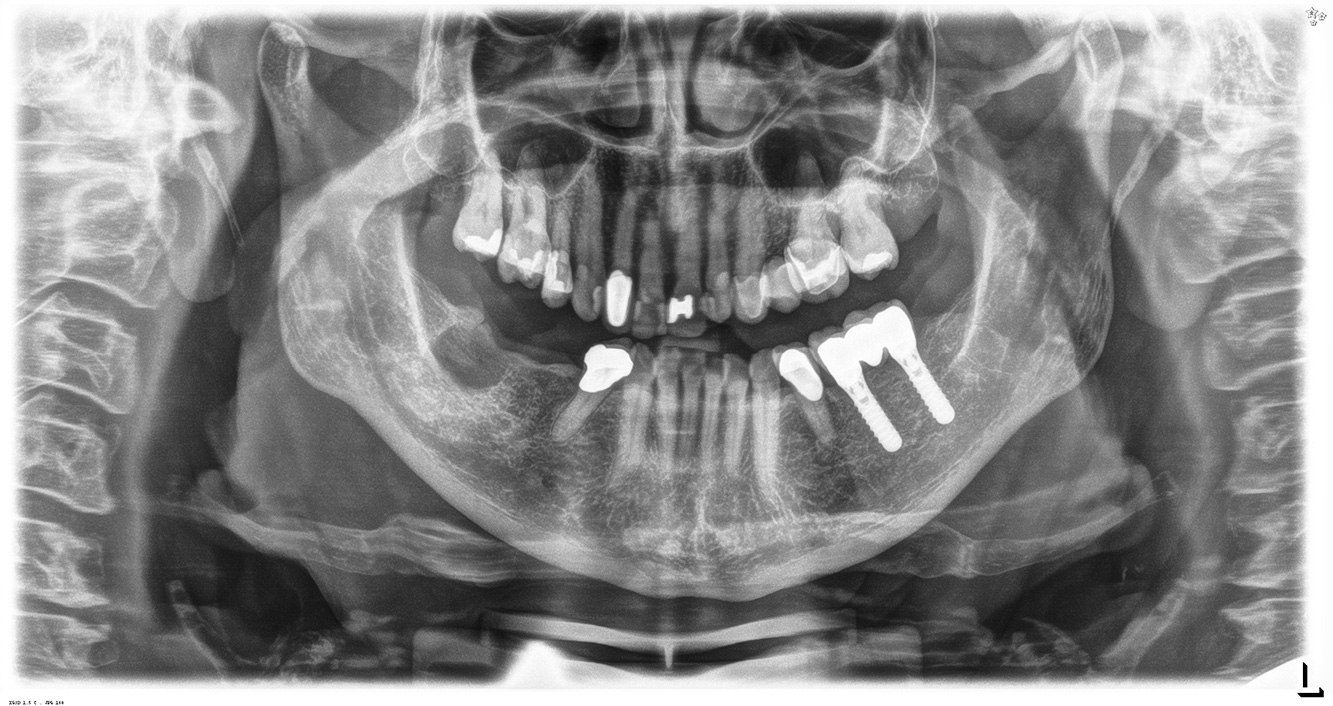

Der gesunde Patient mit parodontaler Vorerkrankung & Periimplantitis

Ein 52-jähriger Patient stellt sich zur Präventionssitzung vor. Der Patient hat keine Allgemeinerkrankungen und nimmt keine Medikamente ein. Er hat verschiedene zahnärztliche Versorgungen und zudem zwei aktive kariöse Läsionen. Außerdem verfügt der Patient über vier Implantate (2., 3. und 4. Quadrant). Es zeigt sich eine parodontale Vorerkrankung (Stadium IV, Grad B). Derzeit herrschen stabile parodontale Verhältnisse, lediglich am Implantat regio 36 zeigen sich Sondierungstiefen (ST) von 5 mm. Zudem lässt sich eine Gingivitis feststellen. mehr Infos